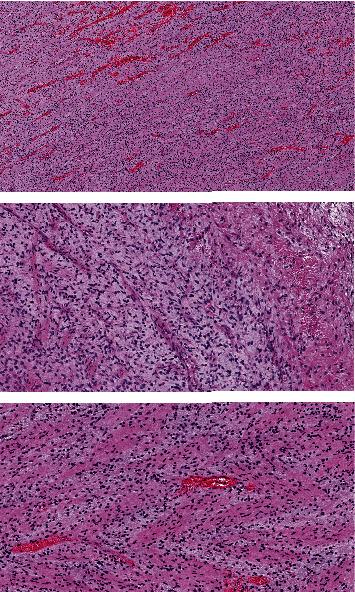

Malignant cardiac tumors are extremely rare, representing only 25% of all cardiac tumors, and angiosarcoma is the most common subtype. Myxofibrosarcomas are one of the rarest forms of cardiac malignant tumors. These tumors can silently grow and produce no or few symptoms until the tumor is large enough to obstruct blood flow. The definitive treatment is negative margin resection, if possible. Most cardiac tumors have a limited response to chemotherapy and radiotherapy. Therefore, surgical treatment is considered the best option. Our patient is a 57-year-old Caucasian postmenopausal female who presented with dyspnea, shortness of breath, and fatigue. Echocardiography confirmed the presence of a mass in the left atrium. A median sternotomy was performed with aortic and bicaval cannulation. Right atriotomy was performed, and the left atrium was exposed through the transseptal approach. A rounded smooth-surfaced mass was found in the left atrium that was 3.5 × 4.5 cm in size. The mass had a prominent and firm attachment point with a wide-based stalk in the pulmonary vein-right atrium border area. The tumor was completely excised, and the excision point was strengthened with a running suture. The following pathologic diagnosis was finally made: myxofibrosarcoma, FNCLCC (National Federation of Cancer Centres) Grade 2. Immunohistochemistry showed positivity for Epithelial membrane antigen (), desmin, calretinin, Ki67, Smooth Muscle Actin (), and S100. Given the rarity of cardiac malignant tumors, we thought preoperatively that this particular tumor could be a myxoma although it did not have the classical attachment point with a stalk at the interatrial septum. Our case is an example of how fast a cardiac sarcoma can grow. Nine months before the presentation, the patient underwent an echocardiography that did not show any signs of tumor growth. The estimated time of growth was 9 months or less. We followed our patient, performing a computer tomography scan and echocardiography 1 month after surgery, and these did not show any signs of tumor growth.

恶性心脏肿瘤极为罕见,仅占所有心脏肿瘤的25%,血管肉瘤是最常见的亚型。黏液纤维肉瘤是心脏恶性肿瘤中最罕见的形式之一。这些肿瘤可悄然生长,在肿瘤大到足以阻塞血流之前不产生或仅产生很少症状。如果可能,确定性治疗是切缘阴性切除。大多数心脏肿瘤对化疗和放疗反应有限。因此,手术治疗被认为是最佳选择。我们的患者是一名57岁的白种人绝经后女性,表现为呼吸困难、气短和乏力。超声心动图证实左心房存在肿块。采用主动脉和双腔静脉插管进行正中胸骨切开术。进行右心房切开术,并通过经房间隔途径暴露左心房。在左心房发现一个大小为3.5×4.5厘米的圆形、表面光滑的肿块。该肿块在肺静脉 - 右心房边界区域有一个突出且牢固的附着点,有一个宽基底蒂。肿瘤被完全切除,切除点用连续缝合加强。最终做出如下病理诊断:黏液纤维肉瘤,法国国立癌症中心联合会(FNCLCC)2级。免疫组化显示上皮膜抗原()、结蛋白、钙视网膜蛋白、Ki67、平滑肌肌动蛋白()和S100呈阳性。鉴于心脏恶性肿瘤的罕见性,我们术前认为这个特殊肿瘤可能是黏液瘤,尽管它没有在房间隔处带有蒂的典型附着点。我们的病例是心脏肉瘤生长速度有多快的一个例子。在就诊前九个月,患者接受了超声心动图检查,未显示任何肿瘤生长迹象。估计生长时间为9个月或更短。我们对患者进行了随访,术后1个月进行了计算机断层扫描和超声心动图检查,这些检查未显示任何肿瘤生长迹象。